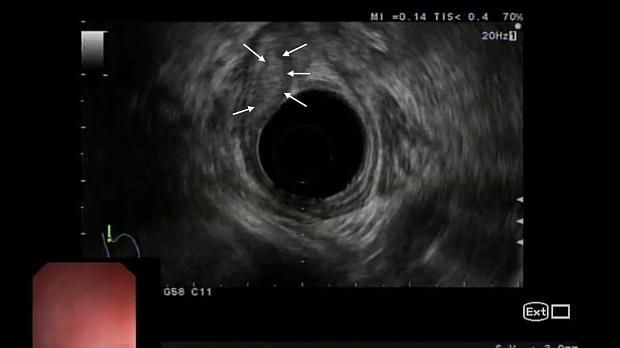

Иллюстрация №6: Рис. 5. Эндоскопическая ультрасонография: опухоль исходит из слизистого слоя, подслизистый слой прослеживается фрагментарно, мышечный слой интактен

Для оценки глубины инвазии опухоли в стенку пищевода и желудка, а также для характеристики регионарных лимфоузлов была выполнена ультрасонография эхоэндоскопом с радиальным УЗ-датчиком (частота 5-10 МГц). По результатам исследования в области кардиоэзофагеального перехода по передней полуокружности определялось гипоэхогенное образование до 15 х 20 мм, исходящее из слизистого слоя стенки, подслизистый слой прослеживался фрагментарно, мышечный слой был сохранен, интактен, наружный контур стенки пищевода и желудка ровный, четкий (рис. 5). Увеличенные и патологически измененные лимфатические узлы не определялись.